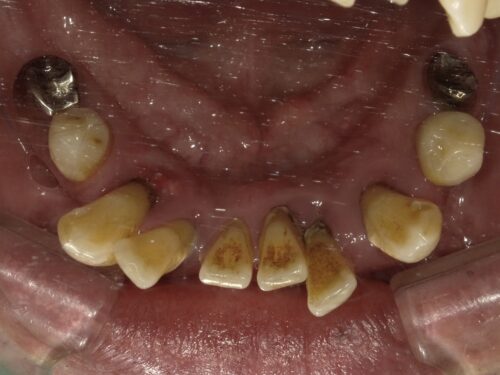

歯周病で歯がグラグラしてしまって来院された患者さんです。

長年お悩みだったようです。

グラグラしてる影響か、前歯が傾いてきてしまっています。

歯ぐきの周りに歯石がついているのが見えます。

歯ぐきも赤く腫れ上がっていますが、

歯周病はそこまで痛みがないので

気づかないうちにここまで進んでしまっていた、なんてこともよくあります。

自覚症状は強くないですが、

重度歯周病の歯はほうっておくとどんどん周りの骨を溶かしていってしまうので、

抜歯をすることで骨の炎症を治さなければなりません。

奥歯も残っていますが歯周病で根元まで見えてしまっていたり、

歯の向きが変わってしまっているところもあります。

下の大臼歯とよばれる奥歯はもうありませんでした。